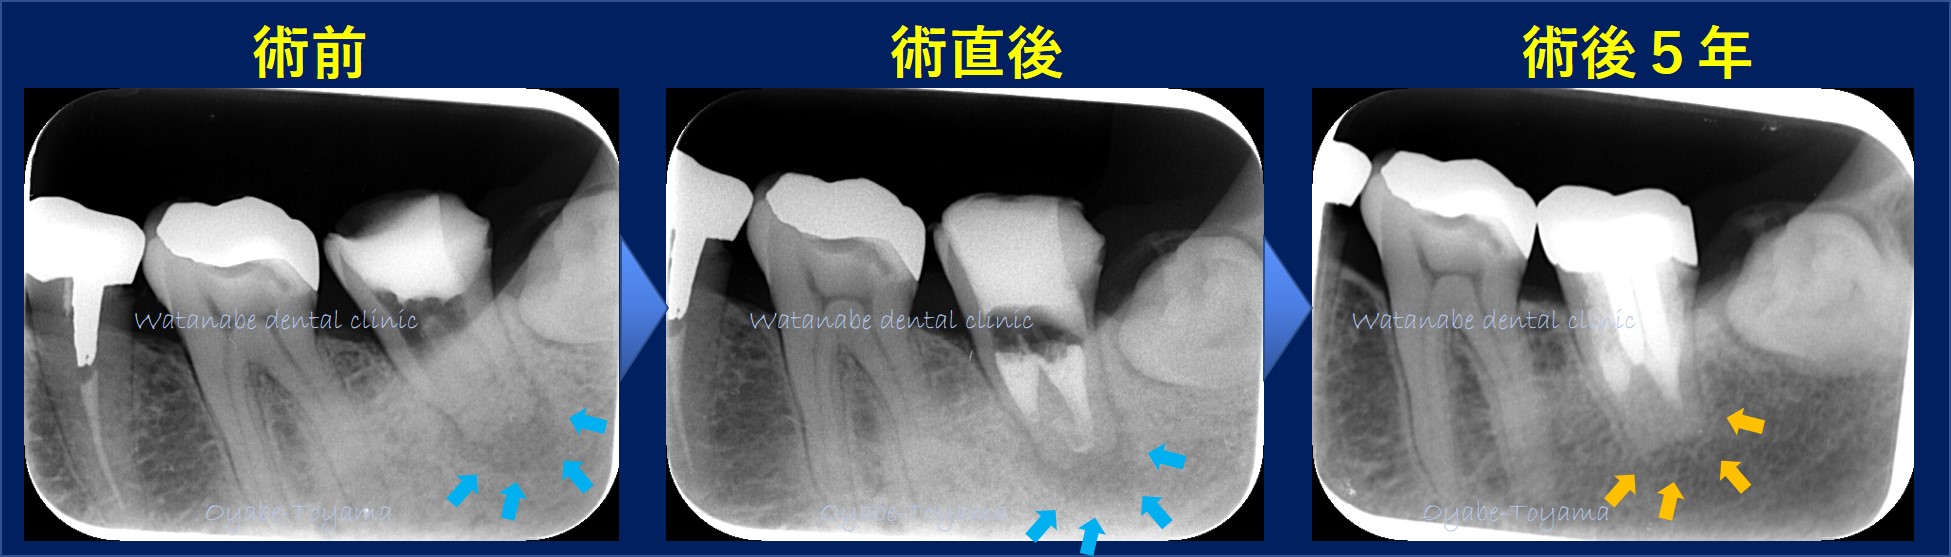

根管治療のケースです。

術前写真(左)では、根の先に黒い影(骨が喪失した部分)が確認されます。これは、根管内に細菌感染が起こっているためです。

術直後(真ん中)では、根管内の細菌はおおむね取り除けているはずですが、まだ黒い影(骨が喪失した部分)が確認できます。

術後3~6ヶ月かけて骨再生が起きるため、術直後では骨の再生は確認できませんでしたが、術後5年(右)では、オレンジ矢印部分の黒い影がなくなり骨が再生されていることが確認できます。

当院では、できるだけ確実な根管治療(保険治療)を行えるように、CT撮影やマイクロスコープを使って治療しています。